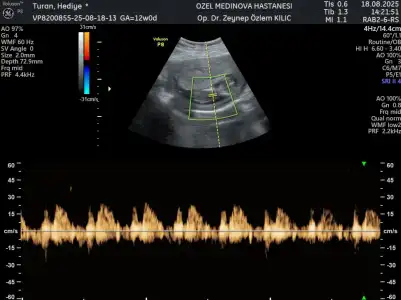

Merhaba yeni görüntüler var sizce ne olabilir doktorum bir tahminde bulundu ama sizin fikrinizi merak ediyorum

Banada tahminde bulunabilir misiniz? Kendi doktorum erkeğe benziyor başka bir doktor kıza benzettiği söyledi

Dojtorunuz ölçüm çizgisini hep cinsiyet kısmına denk getiriyor, yine aynı olmuş 🤦🏻‍♀